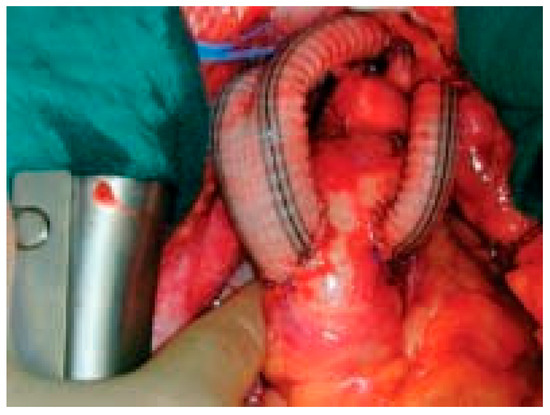

The left subclavian artery is either transposed into the left carotid artery or revascularised at the end of the procedure using an additional 8 mm graft (Figure 3 and Figure 4).

Figure 4. Intraoperative view at the end of the procedure.